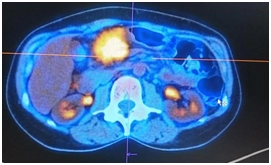

ПЭТ/КТ

Гиперметаболический процесс в утолщенных стенках ободочной кишки и окружающей клетчатке – может соответствовать опухолевому процессу.